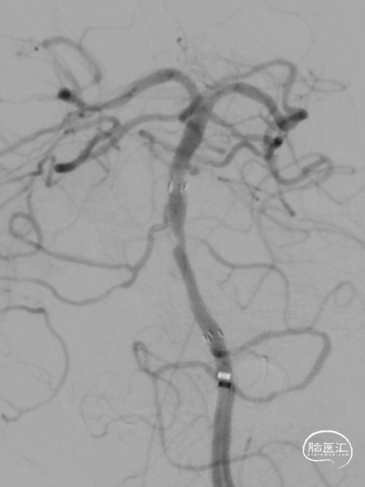

第一次取栓后,血管未通,但明确支架内狭窄位置,交换引入头端塑形的300cm 0.014in微导丝,撤出微导管,沿微导丝引入2.0mm*15mm Sprinter球囊,扩张后狭窄明显减轻,但血栓掉落至右侧大脑后动脉起始部。

交换再次引入加奇4.0mm*30mm Syphonet®取栓支架并释放。

第二次拉栓后造影,血管再通,支架内再狭窄处理风险极高,且目前前向血流3级,对比造影时影像支架未有移位。